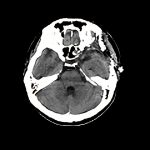

髄膜腫

(海綿静脈洞部)

断層撮影

手術前1

手術後

No.’13_53 手術前1

No.’13_53 手術後